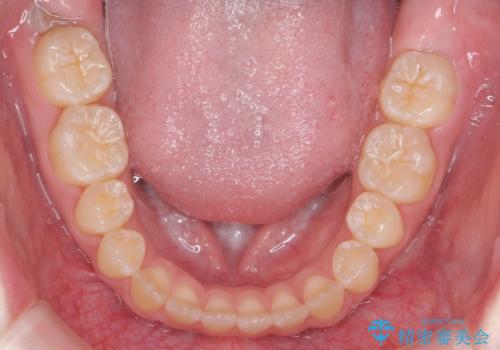

隙間を閉じる際、奥歯が倒れたため、途中ワイヤー矯正を併用しています。

上の前歯の隙間を閉じながら前歯を後方に下げているため、口元もひっこみ、口が閉じやすくなりました。